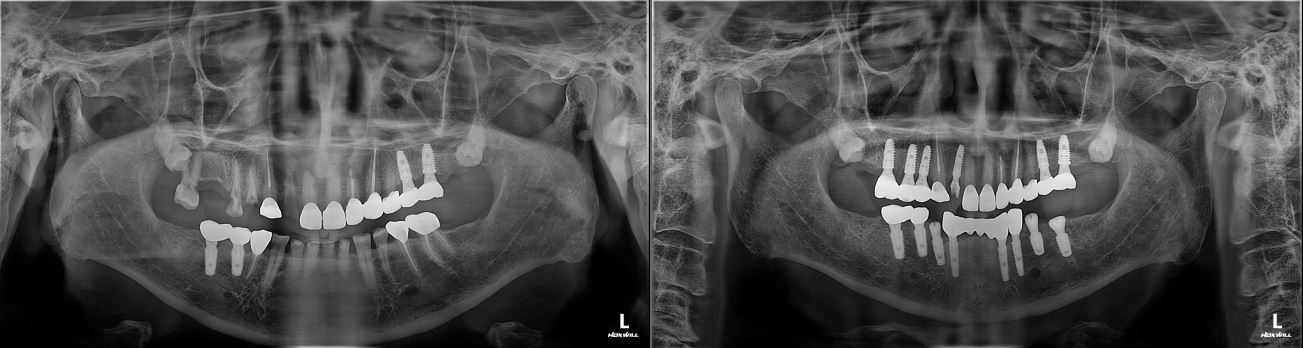

치료전후사진